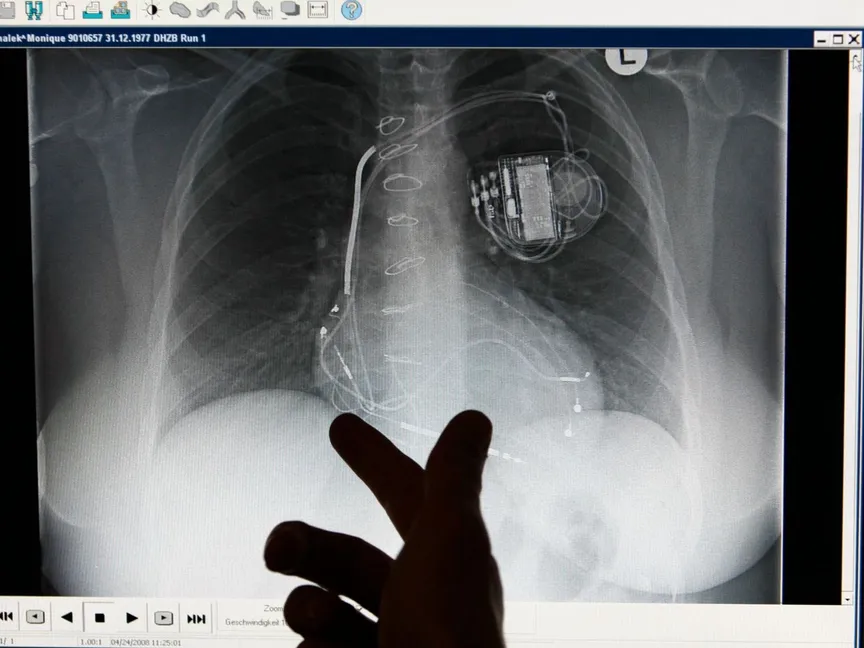

لكن فشل القلب قد يكون مهدداً للحياة. وقد تظهر على الأشخاص المصابين بفشل القلب أعراض خطرة. وقد يحتاج بعض الأشخاص إلى الخضوع لزرع القلب أو تركيب جهاز لمساعدة القلب على ضخ الدم.

يُسمى عدم انتظام ضربات القلب اضطراب النظم القلبي. قد يؤدي عدم انتظام ضربات القلب إلى تسارع ضربات القلب، ما يجعل القلب يعمل بجهد أكبر. قد يؤدي بطء ضربات القلب أيضاً إلى فشل القلب. ويمكن أن يساعد علاج عدم انتظام ضربات القلب على إيقاف فشل القلب لدى البعض.